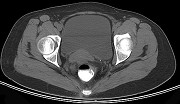

- 单项选择题男,67岁, 排便习惯改变,血便三个月入院, CT检查如图所示,下列说法错误的是  (    )

- A、直肠肠腔局限性增厚

- B、其表面欠光整,边界欠清晰

- C、可做直肠指检及活检以确定病变性质

- D、此为直肠息肉

- E、此为直肠癌